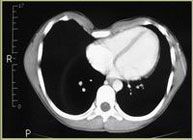

Síntomas cardiacos:

- Soplos funcionales

- Bloqueos I de rama

- Dextrorrotación